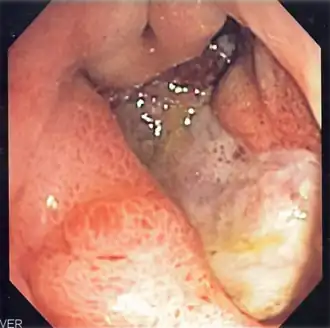

![]() Endoscopic still of esophageal ulcers seen after banding of esophageal varices, at time of esophagogastroduodenoscopy | |